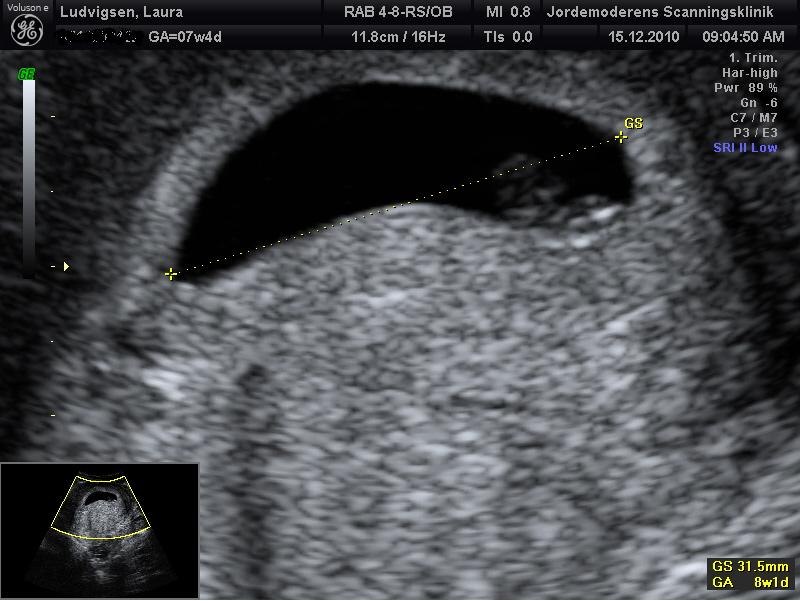

nu glæder jeg mig da helt vildt til i morgen, der er jeg 7+5 og skal scannes det blir lidt sjovt, og dine billeder er meget fine og grunden til at de er forskellige er bla. vinkler og det pres der bliver på/i maven under en scanning, og ja man kan godt se det er en begyndende baby du har der så tillykke